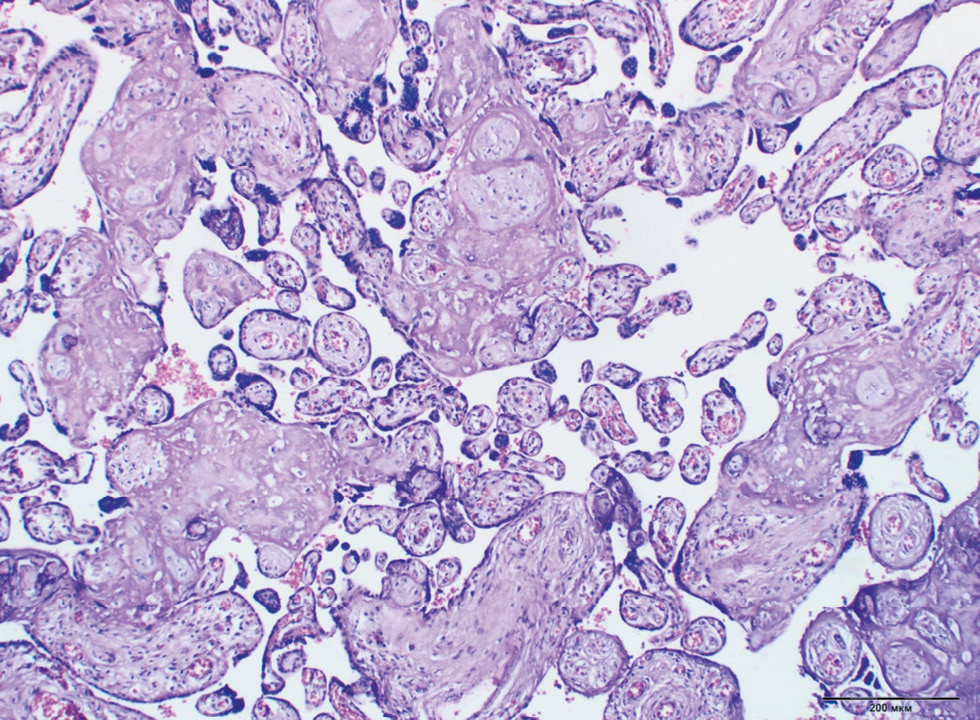

In Groups 2 (type 1 DM on MII) and 3 (type 2 DM on a diet), a high degree of fibrinoid deposition in the intervillous space was revealed significantly more often than in other groups (16.6% and 18.9% of cases, respectively). Meanwhile, the deposition of fibrinoid in the subchorial space was more typical for Groups 3 (type 2 DM on a diet) and 5 (GDM on a diet), namely, in 38.9% and 40.4% of cases, respectively (Fig. 3).

Fig. 3. Fibrinoid villous alteration in type 1 DM on multiple insulin injections. Staining with hematoxylin and eosin, ×100